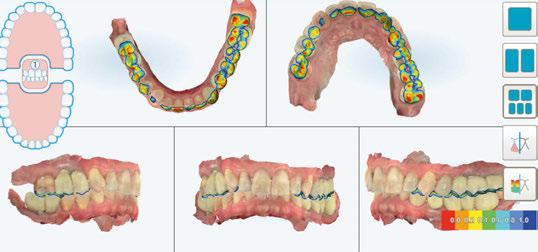

A los 4 meses, se retiró la prótesis provisional, verificando la

estabilidad de todos los implantes y procediendo a la toma de impresión definitiva, enviando toda la información necesaria, tanto de la posición de los implantes, de los perfiles de emergencia y pónticos y de la forma del provisional (Figuras 28 y 29).

Para ello, se procedió al escaneado mediante el escáner intraoral iTero Element™2 de los siguientes elementos:

Figura 28. Provisional en boca a los 4 meses.

Figura 29 (a, b, c). Perfiles de emergencia tras la retirada del provisional.

-Escaneado 1 superior (preescaneado): provisional atornillado en boca.

-Escaneado inferior: antagonista.

-Escaneado de mordida izquierda y derecha.

-Escaneado 2 superior: con los scanbodies atornillados a los pilares cónicos TSV-TM de Zimmer®.

-Escaneado HD de cada scanbody individualmente.

-En un escaneado nuevo, se procedió a la captura del provisional fuera de boca, para poder alinearlo con el escaneado 1 (pre-escaneado) y tener bien definidos los perfiles de emergencia (Figuras 30-34).

En la siguiente visita se solicitó, por un lado, una prueba de verificación del escaneado y una prueba estética rígida en resina, ya que habíamos solicitado modificaciones del provisional.

Figura 32. STL obtenidos mediante iTero Element™2.

Figura 33. Ortopantomografía con scanbodies posicionados en boca.

Figura 34. Archivo STL de la férula de verificación previo a su fresado.

Figura 30. Scanbodies posicionados en boca. Vista oclusal. Figura 31. Scanbodies posicionados en boca. Vista frontal.

superventas con un plus.

Visiblemente diferente. Notablemente mejor.

Fresado en seco con un plus. Rectificado y fresado en húmedo con un plus.

Visiblemente diferentes y notablemente mejores, los dos superventas de nuestra PERFORMANCE CLASS garantizan una precisión excelente para cualquier aplicación, ya sea en el laboratorio dental, en la consulta o en el centro de fresado. La K5+ es la fresadora compacta y de alta calidad para el mecanizado en seco de sus discos. Se complementa de forma óptima con la N4+ para el procesamiento en húmedo de bloques. Como dúo, puede cubrir prácticamente todas las indicaciones con estas dos fresadoras. Más información: www.vhf.com

Figura 35. Imagen de la férula de verificación.

Figura 36. Férula de verificación atornillada al modelo.

Figura 37. Férula de verificación atornillada en boca.

Figura 38. Prueba de dientes rígida (PDR) de la rehabilitación final.

Figura 39. PDR en oclusión.

Figura 40. Posición bordes incisales con la PDR.

Figura 41. Posición bordes incisales en reposo.

Figura 42. Diseño de la estructura metálica.

Figura 43. Prueba de la estructura metálica.

Figura 44. Prueba de «biscuit».

Figura 45. Prótesis definitiva metal-cerámica.

Figura 46. Relación prótesis y perfiles de emergencia.

Figura 47. Prótesis definitiva atornillada en boca.

Figura 48. Prótesis definitiva atornillada en boca con fondo negro.

Figura 49. Ortopantomografía final.

Una vez validada la prueba estética, se pidió la estructura metálica de cromo-cobalto, la cual se probó en boca y se realizaron las verificaciones a partir de radiografías periapicales.

Posteriormente, se realizó la prueba de «biscuit» y se solicitó el acabado. El día de la entrega, se atornilló la prótesis a 20 N, se taparon las chimeneas con teflón y composite y se comprobó nuevamente la oclusión. Posteriormente, se entregaron las recomendaciones de prótesis sobre implantes fija, enseñando instrucciones de higiene oral y programando la primera visita de control a los 15 días (Figuras 35-49) (Cuadro 2).

DISCUSIÓN

El tratamiento de casos de Implantología inmediata múltiple requiere de un enfoque multidisciplinario. Para que el tratamiento sea exitoso desde el punto de vista funcional, biológico y estético, necesitaremos abordar el caso desde un punto de vista de la Cirugía, la Periodoncia y la Prótesis.

El uso de tecnologías digitales nos facilita la comunicación del caso entre profesionales y entre profesional y paciente.

Cuando realizamos una exodoncia, siempre se producirán cambios anatómicos en el alveolo, tanto de los tejidos duros como blandos. Estos pueden ser: reducción de anchura y altura en un 25% en el primer año y en un 50% a los tres años (2/3 partes en los 3 primeros meses); los mayores cambios dimensionales se producen durante primer año, unos 5-7 mm de pérdida (50%) (13); existe mayor reabsorción en la cortical vestibular que en lingual; y existe mayor reabsorción horizontal (3,8 mm) que en vertical (1,24 mm).

Para intentar reducir o compensar dichos cambios podemos recurrir a diferentes técnicas, como las de preservación alveolar y regeneración alveolar (14-16). En los casos en que las condiciones sean favorables, podremos realizar una Implantología inmediata y provisionalización inmediata. Para decidir qué técnica quirúrgica será más indicada en cada

Cuadro 2. Protocolo implantes inmediatos múltiples y carga inmediata.

caso, deberemos de evaluar cada uno individualmente, basándonos en una correcta planificación.

Los factores que deberemos de evaluar en cada caso serán: motivo de la exodoncia/cirugía flapless; presencia de infección activa; estabilidad primaria del implante inmediato/posición 3D; estado de tabla ósea vestibular; biotipo periodontal del paciente; presencia de defectos en los tejidos blandos; posibilidad de provisionalización inmediata; y necesidades estéticas y psicológicas.

El primer paso consistirá en realizar una exodoncia lo más atraumática posible, conservando las corticales vestibular y palatina intactas (17). La cortical vestibular de los dientes anteriores superiores

presentará en el 87% de los casos una anchura media inferior a 1 mm (18). En muchas ocasiones podremos encontrarnos con defectos de las tablas óseas o tejidos blandos, debido a fracturas verticales o reabsorciones radiculares, donde deberemos tratar los defectos presentes mediante técnicas de regeneración alveolar, en algunos casos, difiriendo la colocación del implante. Siempre que podamos realizaremos la exodoncia y la colocación de los implantes mediante cirugía flapless, manteniendo la vascularización proveniente del periostio, reduciendo así la posible pérdida ósea de las corticales (19-21).

Para poder realizar una Implantología inmediata, se recomienda una estabilidad primaria entre 30-35 Nm. El primer paso

«En casos de Implantología inmediata es necesario el correcto manejo tanto de los pónticos como de los gaps para reducir los cambios dimensionales producidos después de una exodoncia»

Para conservar la arquitectura ósea presente será importante el manejo del gap y los alveolos que harán de pónticos.

En el caso clínico presentado, posicionamos los implantes ligeramente palatinizados, de diámetro reducido y dejando un gap mínimo de 2 mm en todos ellos (23). Posteriormente, rellenamos todos los gaps y alveolos pónticos con biomateriales de lenta reabsorción, compensando así la remodelación de las corticales óseas (24, 25).

será el estudio, a partir del CBCT, de la disponibilidad ósea en la porción apical y palatina del alveolo postextracción para cada implante. En el caso presentado se puede observar la correcta disponibilidad ósea para cada posición planificada (20).

En los casos de arcadas completas como el que hemos presentado, la mayor complejidad es la posición tridimensional correcta de los implantes, ya que, al realizar las exodoncias, podemos perder las referencias anatómicas. Es por este motivo que, nuestro protocolo de trabajo en estos casos, empieza por una planificación y encerado digital para la correcta posición de los implantes, enterrándolos unos 4 mm respecto al LAC de los dientes adyacentes (si los tejidos son óptimos) o a 4 mm del margen cervical de la restauración protésica final en casos de edéntulos totales (21, 22). Para ello, trabajaremos con cirugía guiada, tanto en las fases de reconstrucción ósea como en la cirugía de implantes, pudiendo ser así más precisos.

Es importante valorar el fenotipo periodontal del paciente, ya que la presencia de un fenotipo grueso aporta estabilidad a los tejidos tanto blandos como duros tras una exodoncia. Por lo tanto, deberemos mejorar siempre la cantidad y calidad de los tejidos mediante un injerto de tejido conectivo (ITC) en los pacientes con biotipo fino y será recomendable también en fenotipos gruesos para compensar la remodelación de los tejidos duros, en los casos de corticales vestibulares inferiores a 2 mm (26). Igualmente, los casos con recesiones de los tejidos blandos, deberemos tratarlos con ITC, pudiendo realizar una Implantología inmediata siempre que estos sean inferiores a 3-4 mm (27).

Como ya hemos mencionado, nuestro protocolo de trabajo consistirá en la realización de una Implantología inmediata, y siempre que las condiciones sean favorables para una provisionalización inmediata. En los casos unitarios y parciales, realizaremos una provisionalización sin función, eliminando los posibles contactos oclusales. En los casos de edéntulos totales, dicho provisional entrará en oclusión desde el primer día, por lo que será importante comprobar el correcto ajuste oclusal tanto en

Escanea el código QR con tu smartphone para acceder al listado de precios o accede a www.expadent.com/precios

YA DISPONIBLE EXPADENT APP

Hemos mejorado nuestro sistema de gestión, y ahora cualquiera de nuestros clientes podrán realizar los pedidos directamente desde nuestra aplicación, intuitivamente.

También permite hacer un seguimiento total del proceso de fabricación y de envío del pedido realizado. CORONA ZIRCONIO MULTICAPA 49,90 euros …y como siempre con los precios más competitivos del mercado

relación céntrica como en movimientos de lateralidad y protusiva. En nuestro caso, enviamos el provisional al laboratorio para realizar el acabado y pulido de los perfiles de emergencia y pónticos, entregándolo a las 24 horas. La realización de éste aportará una serie de ventajas, mencionadas anteriormente como (28-30): el sellado de los alveolos y el aislamiento de los biomateriales; el acondicionamiento de los tejidos periimplantarios desde el primer día; y una estética y mejora en los aspectos psicológicos del paciente. Habrá que tener especial cuidado en el manejo de los perfiles de emergencia y de los pónticos paras evitar posibles contracciones de los tejidos blandos. Deberemos de diferenciar las partes de nuestro perfil de emergencia, dejando la zona subcrítica lo más estrecha posible para dejar espacio al coágulo y al injerto de tejido blando, y la zona crítica con el perfil deseado o ligeramente reducido, para mantener o recrear la arquitectura gingival final deseada (31-33).

CONCLUSIONES

Hoy en día, los protocolos en casos de Implantología inmediata y provisionalización inmediata en casos de edéntulos totales son predecibles,

siempre que se sigan unos protocolos adecuados.